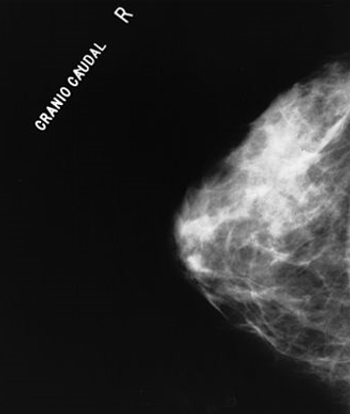

A physician’s age may have an effect on his or her opinions about the effectiveness of breast cancer screening methods, including self-exam and mammography.

At MBCC, one presenter made the argument for screening mammography for all women starting at the age of 40, despite the controversy surrounding the topic.

As part of our MBCC coverage we discuss MRI screening for breast cancer in patients who carry a BRCA mutation or have a first-degree relative who is a BRCA carrier.